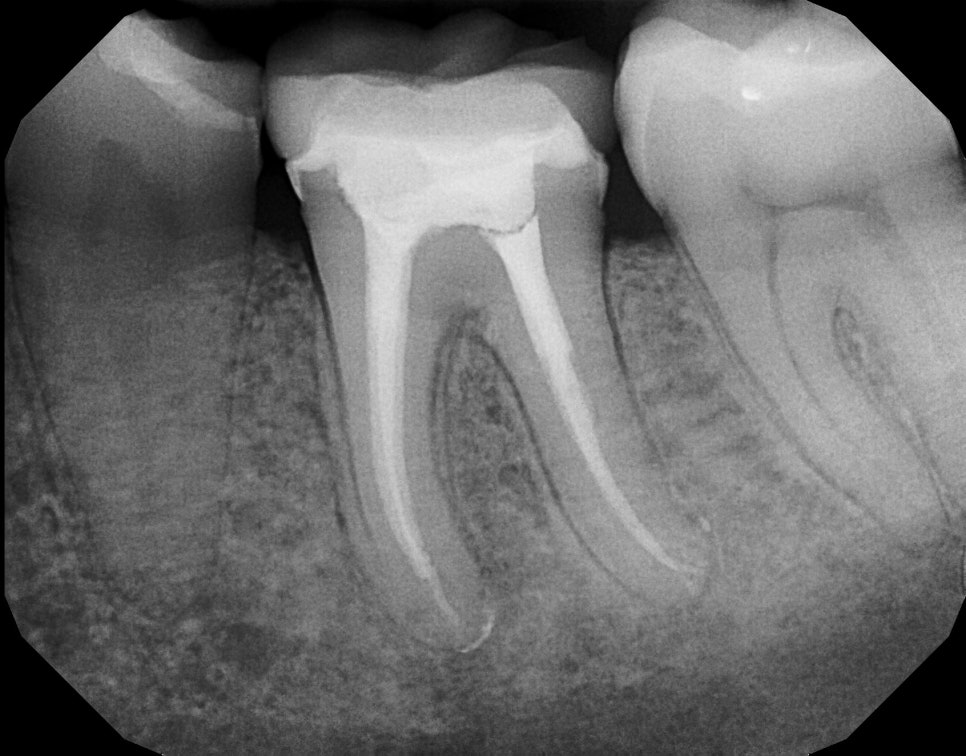

신경치료가 된 치아를 엑스레이로 찍은 상태입니다. 보시는것처럼다른부분보다 유독 흰색으로 되어있는 부분은 신경치료가 된 부분이구요, 기존 신경이 제거되고 생체친화적인 물질로 채워진 모습입니다(출처: https://idealdentalcare.co.uk/)